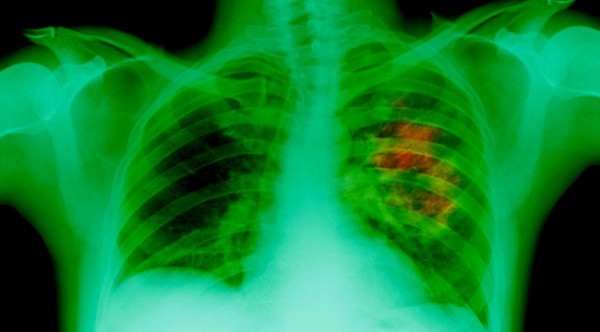

Sharon was afflicted by a minor pain in her left side around her ribs in December of 2013. She attributed her discomfort to a massage she had the previous Friday. When the pain worsened, she decided to get it checked out. Less than a week later, Sharon was diagnosed with non-small cell lung cancer. She also had a significant amount of fluid around her heart, stemming from cancer in the pleural lining of the left lung.

The doctors had discovered a 5 cm primary tumor in her left lung. Lymph nodes inflamed with cancer dotted her chest and lower neck. Following two rounds of chemo, which her doctors noted probably wouldn’t work, Sharon’s prognosis went from bad to worse. She tested positive for EGFR mutation, which precluded her from continuing her original chemo treatment. Instead, she would have to be put on a chemo tablet called Tarceva.

Bi-monthly scans revealed that Sharon’s tumor was gradually shrinking. Her tumor had shrunk from 5 cm in December 2013 to 2.1 cm in July 2014. After seven months of cannabis oil treatment, to her doctors’ obfuscation, Sharon was cancer-free and the fluid around her heart was gone.